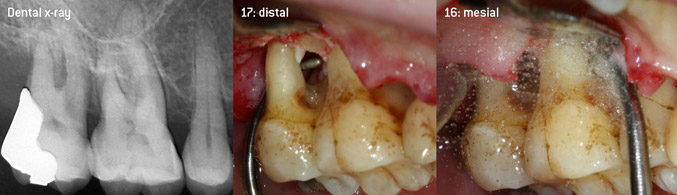

Open debridement of the furcations on teeth 16 and 17

Fig. 3: Open debridement of the furcations on teeth 16 and 17 in case of advanced attachment loss

The aim was to develop a universally applicable tip in order to avoid time-consuming tip changes. In addition, it should be easier to use the new working tips in tight intraosseous pockets from distal and at the distal furcation entrance of maxillary molars, allowing more effective use of instruments as a result. This was achieved by employing an instrument curve with a larger diameter (Figure 1), which is highly advantageous for closed debridement on teeth with advanced attachment loss and involvement of furcation in particular (Figure 4).